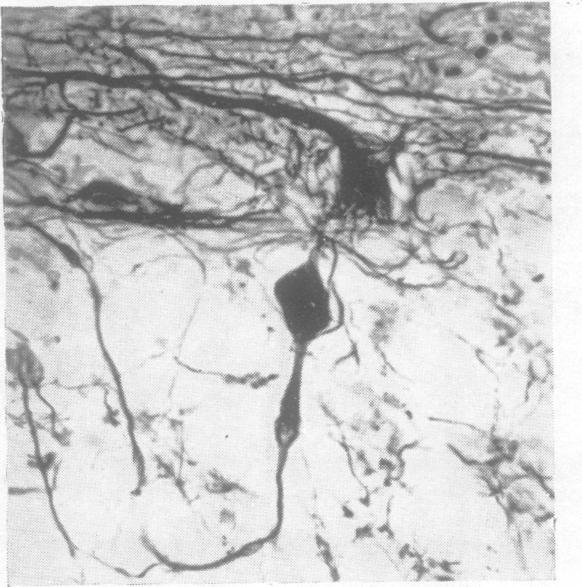

A benign tumour of the cerebellum; report on two cases of diffuse hypertrophy of the cerebellar cortex with a review of nine previously reported cases.

J Neurol Neurosurg Psychiatry. 1955 Aug;18(3):199-213. doi: 10.1136/jnnp.18.3.199.